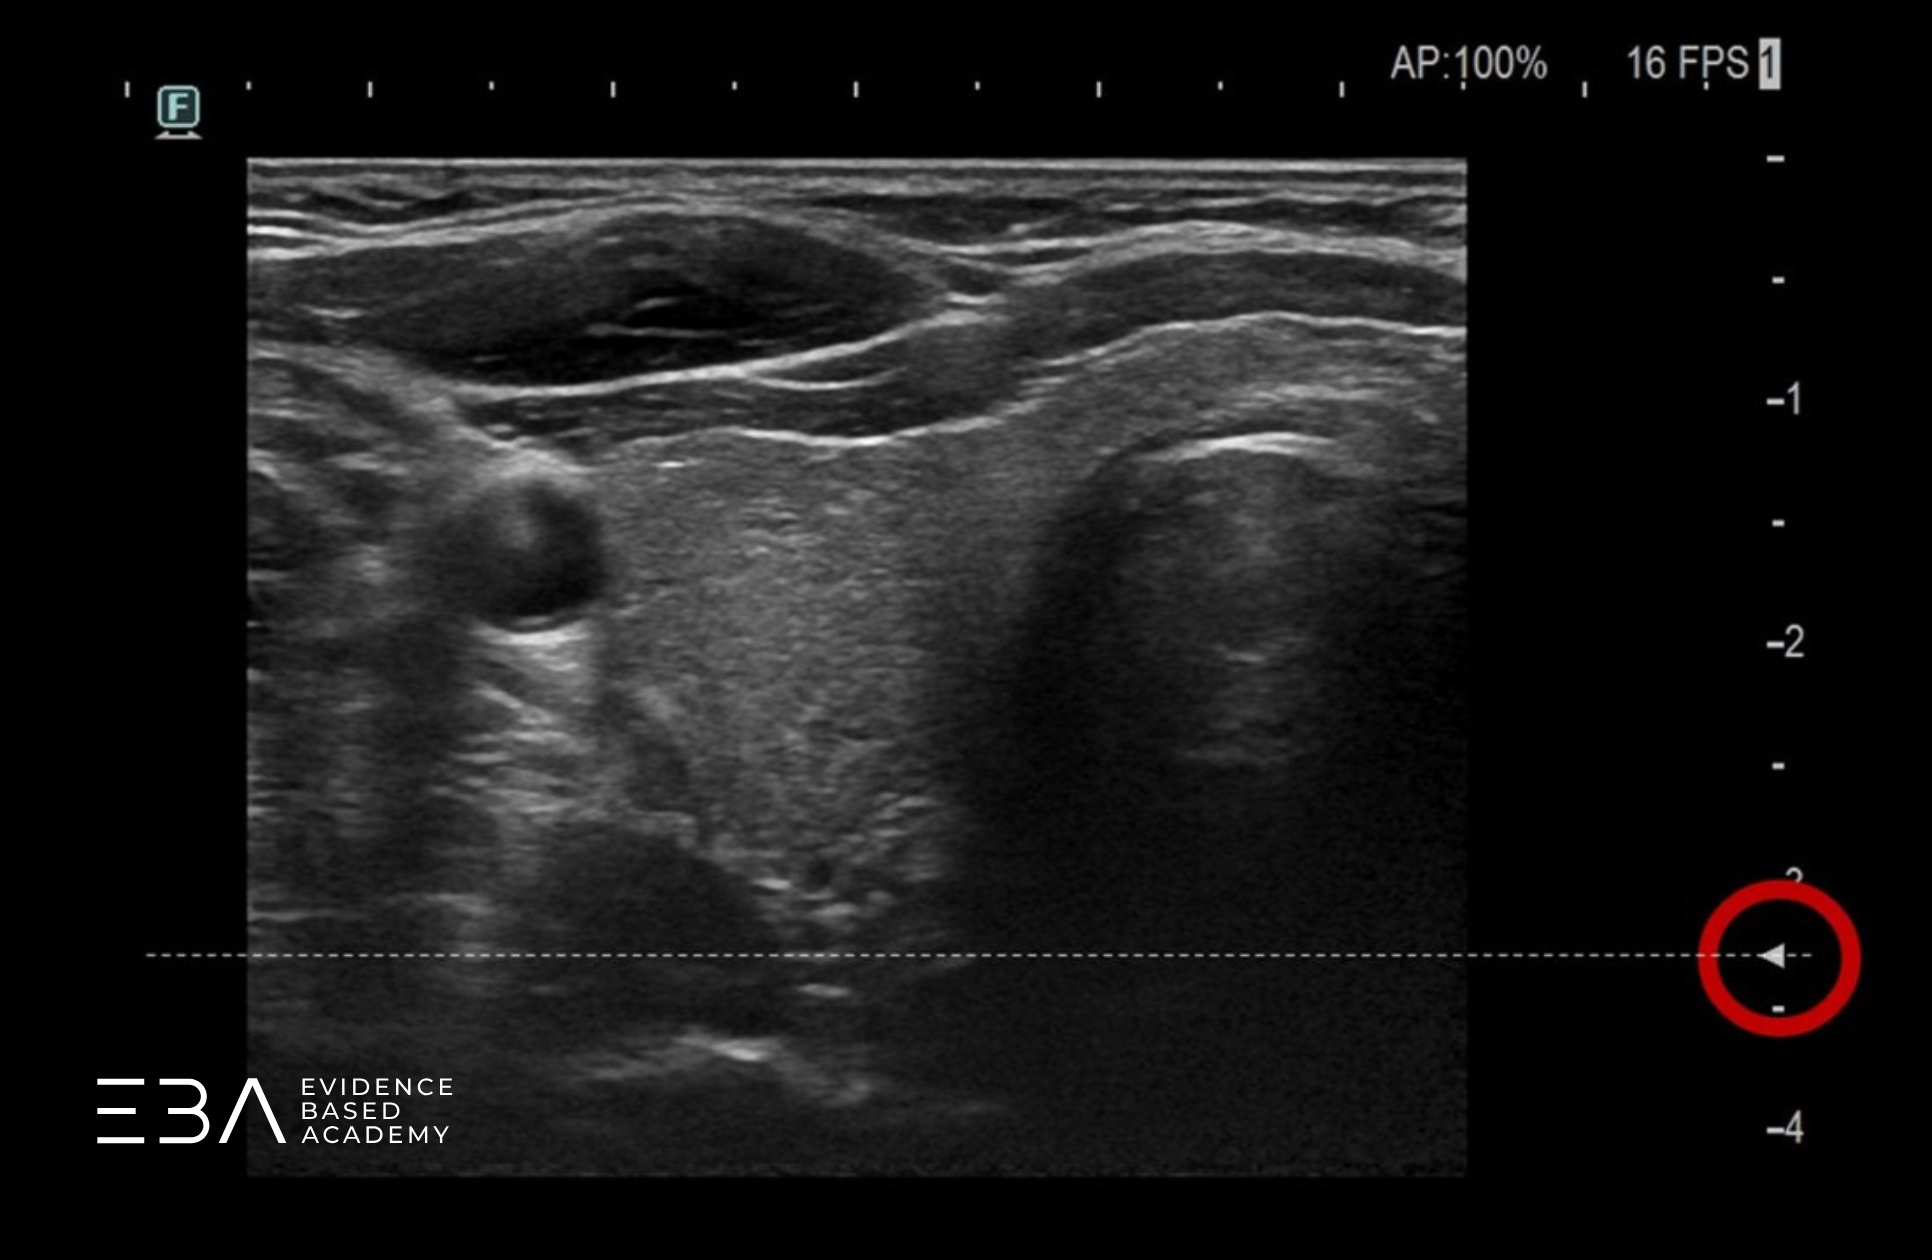

Wiele aparatów oferuje automatyczną opcję pomiaru objętości – „Volume”. Wykorzystujemy ją w połączeniu z podziałem obrazu na dwie części – tzw. „Dual scan”. Dzięki temu na monitorze możemy jednocześnie uzyskać dwa prostopadłe do siebie przekroje potrzebne do uzyskania wszystkich trzech wymiarów płata. Po ich wyznaczeniu aparat sam obliczy objętość.

Wykorzystanie opcji Volume do pomiaru objętości płata.